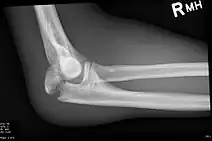

Olecranon fracture is a fracture of the bony portion of the elbow. The injury is fairly common and often occurs following a fall or direct trauma to the elbow. The olecranon is the proximal extremity of the ulna which is articulated with the humerus bone and constitutes a part of the elbow articulation. Its location makes it vulnerable to direct trauma.

To assess an olecranon fracture, a careful skin exam is performed to ensure there is no open fracture. Then a complete neurological exam of the upper limb should be documented.[5][2] Frontal and lateral X-ray views of the elbow are typically done to investigate the possibility of an olecranon fracture.[1] A true lateral x-ray is essential to determine the fracture pattern, degree of displacement, comminution, and the degree of articular involvement.